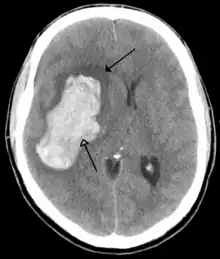

![]() | |

| CT scan of the brain showing a massive, prior right-sided ischemic stroke from blockage of an artery. Changes on a CT may not be visible early on.[1] | |

The most significant risk factor for stroke is high blood pressure.[7] Other risk factors include high blood cholesterol, tobacco smoking, obesity, diabetes mellitus, a previous TIA, end-stage kidney disease, and atrial fibrillation.[2][7][8] Ischemic stroke is typically caused by blockage of a blood vessel, though there are also less common causes.[13][14][15] Hemorrhagic stroke is caused by either bleeding directly into the brain or into the space between the brain's membranes.[13][16] Bleeding may occur due to a ruptured brain aneurysm.[13] Diagnosis is typically based on a physical exam and supported by medical imaging such as a CT scan or MRI scan.[9] A CT scan can rule out bleeding, but may not necessarily rule out ischemia, which early on typically does not show up on a CT scan.[10] Other tests such as an electrocardiogram (ECG) and blood tests are done to determine risk factors and possible causes.[9] Low blood sugar may cause similar symptoms.[9]